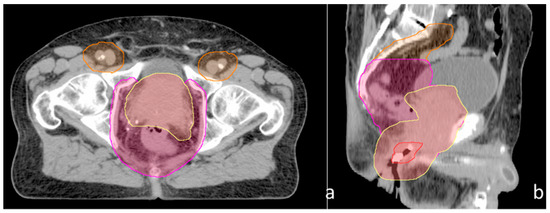

| Structure | Region 1 | Region 2 | Region 3 | Fractionation | Figure 1 |

|---|---|---|---|---|---|

| PTV 36 | Common iliac LNs, inguinal LNs | External iliac LNs, internal iliac LNs, obturator LNs | Prostate, seminal vesicles, anus/peri-anal region | 36 Gy/18 fractions | Orange |

| PTV 45 | External iliac LNs, internal iliac LNs, obturator LNs | Prostate, seminal vesicles, anus/peri-anal region | 45 Gy/25 fractions | Magenta | |

| PTV 50.4 | Prostate, seminal vesicles, anus/peri-anal region | 50.4 Gy/28 fractions | Yellow (anus in red) |